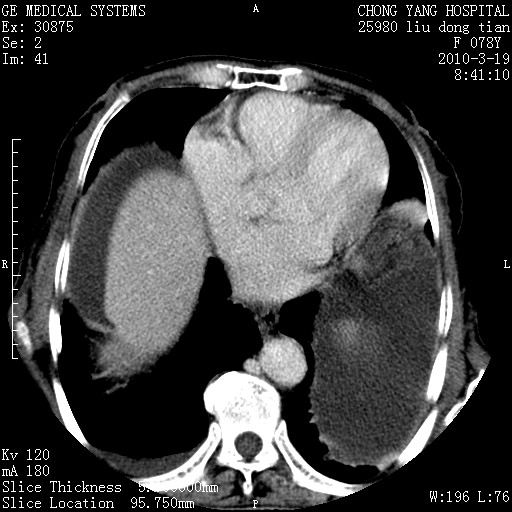

标题: CT25199:F 78Y 腹胀半年 消瘦乏力 [打印本页]

胆囊壁增厚并明显强化,胆囊癌伴多发转移瘤可能性大,淋巴瘤不除外,右肾囊肿,胸腹水.

考虑nhl,肝、脾、腹膜腔及腹膜后多发淋巴结受侵,腹水,右肾囊肿,慢性胆囊炎,右侧少量胸腔积液。

胆囊有软组织影有强化,支持胆囊癌,肝脾、腹膜后淋巴结转移。

nhl的淋巴结多围绕主动脉,而且主动脉会移位,所以不考虑nhl。

分开来讲:肝左叶、尾叶病灶有不均强化像肝癌;

脾脏病灶无强化,像多发囊肿或淋巴管瘤,不除外淋巴瘤(低强化);

胆囊增生性病变:胆囊癌,腺肌增生症,慢性胆囊炎;

肝门、胰腺头、腹膜后多个团块: 淋巴瘤,转移;

腔静脉肝内段细小有无布加可能?

一元论最好了 淋巴瘤所致改变; 胆囊癌转移不像,胆囊周围肝组织清晰,肝癌淋巴结转移?三元论都不止。

最后报的胰头癌多发转移,脾脏单独考虑囊肿或淋巴管瘤。